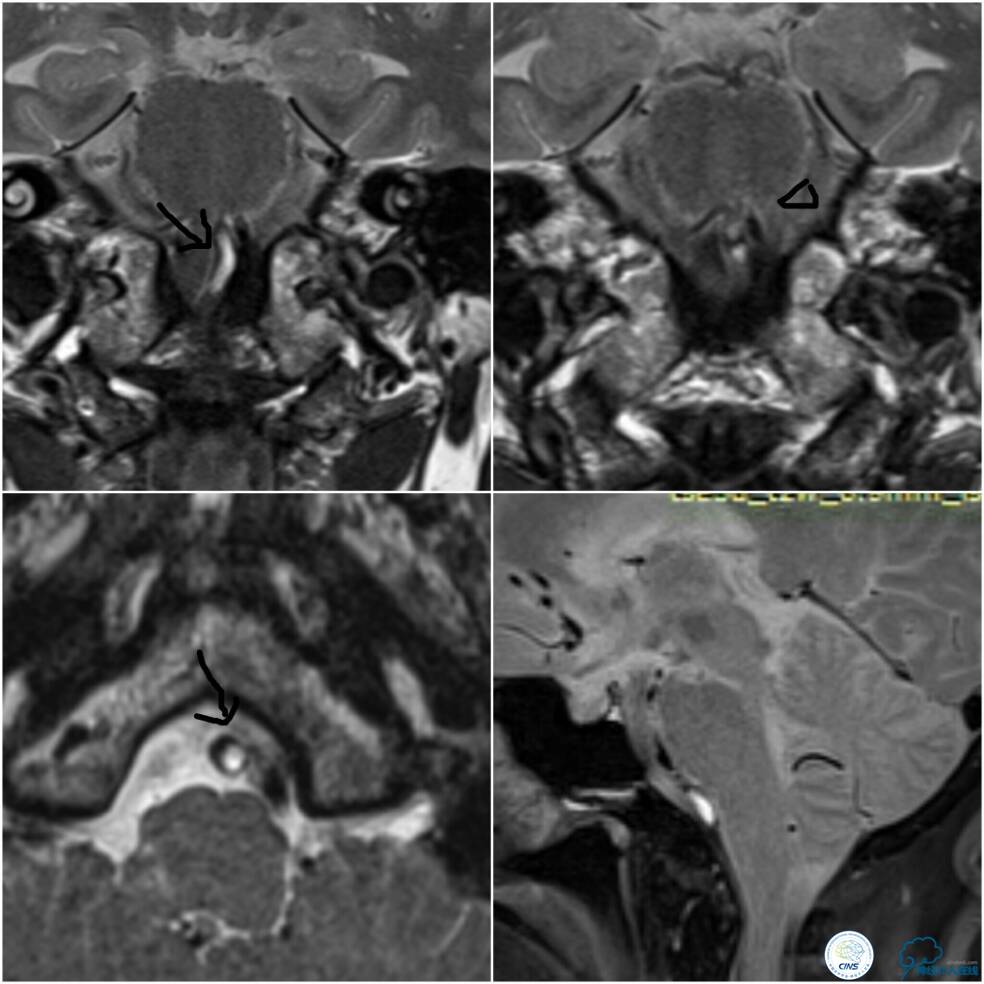

病后就诊当地医院,予以双抗+积极控制危险因素治疗,但症状持续无缓解,就诊期间核磁检查提示右延髓新近脑梗死,MRA示双椎及基底动脉显示欠佳(图1)。

椎基底动脉高分辨核磁提示右椎动脉V4段闭塞,闭塞段管腔内可见高信号(箭头),考虑血栓,左椎动脉V4段至基底汇合处见向心性斑块(三角)(图7)。